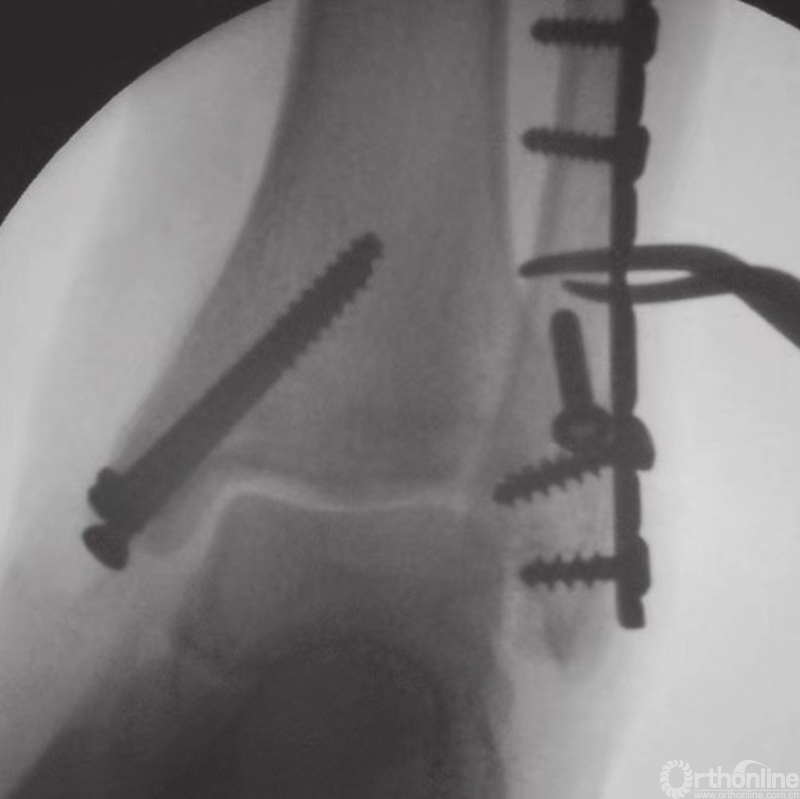

下胫腓联合固定技术

在完成所有踝部骨折的固定之后,应评估下胫腓联合的稳定性。如果下胫腓联合关节上方或下胫腓联合水平发生腓骨骨折,应充分检查下胫腓联合的稳定性。在前后和中外两个平面上,应检查其完整性(图23)。另外,因为下胫腓联合发生损伤时腓骨可能向外旋转,故还应检查腓骨的旋转情况。

图23 用巾钳夹住腓骨向外侧牵拉以评估下胫腓联合的稳定性

如果下胫腓联合不稳,则须进行固定,固定时采用皮质骨螺钉。由于腓骨在解剖关系上位于胫骨的后外侧,因此应将螺钉从后向前以30°的角度嵌入。一般认为,三皮质骨螺钉固定足以保证下胫腓联合的稳定性。螺钉应至少高过关节线2cm(图24和图25)。

图24 下胫腓骨螺钉置入方法

图25 通过钢板的皮质骨螺钉固定旋前外旋型下胫腓联合损伤